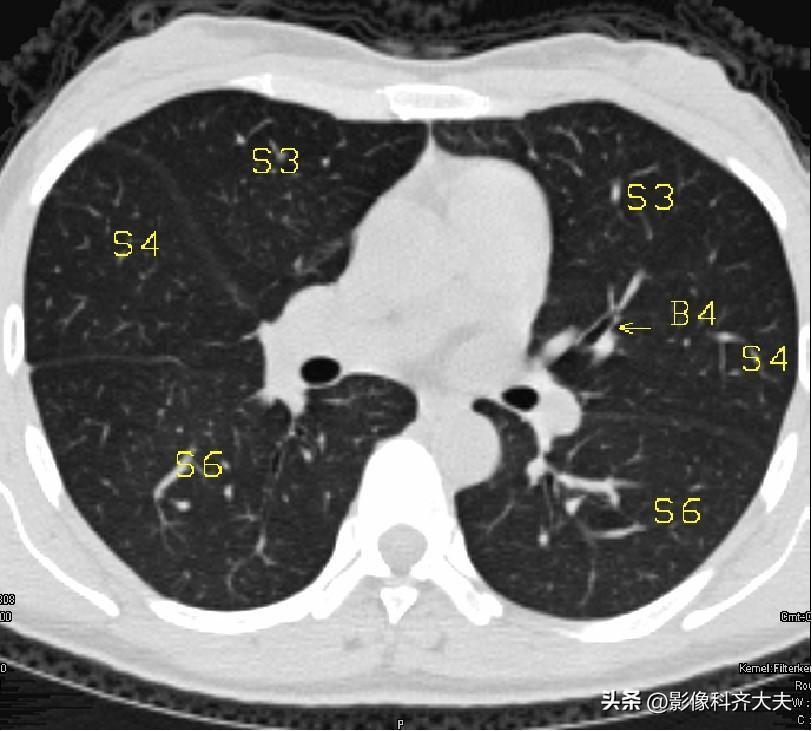

图11-隆突下3cm层面

▲B4:右中叶外侧段/左舌上段支气管